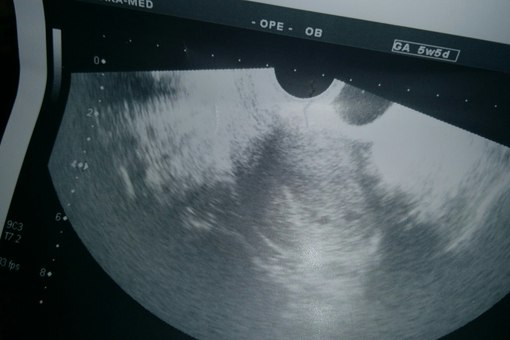

Девочки, всем привет! Кто меня помнит-недавно рассматривали с вами снимки с моего узи, гадали, сколько ж там малышей. Эта неделя показалась просто вечностью... Ночью очень плохо сплю, всякие мысли в голове. Главное, чтоб все было хорошо, чтоб всё развивалось. А сколько-как Бог даст... А вообще, мне не верится, что может быть двое- не было у нас в роду ни двойни, ни тройни. В общем, завтра тайна раскроется...

Просто мысли, сумбур в голове..) а под катом еще раз фото.для тех, кто не видел)))

По форме, плодных два. Зажали кулачки и ждем новости.

На верхнем двое,на нижнем трое!))) удачки на завтра!))

она сказала, что, либо двойня, либо угроза... поэтому я уже на нервах всю неделю... дождаться бы завтра!)))

Вижу 3 кружочка :) Удачи Вам!Ждем новостей